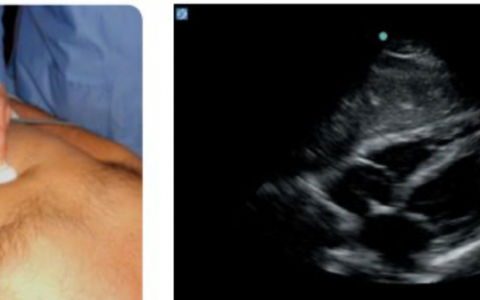

今天的主要内容仍然是有关“重症患者的初始评估”。今天我们对评估的第二部分内容“查体”中重症超声流程里一个很重要的BLUE流程做个详细解读。前头讲过,呼吸急促是最早而且是最重要的临床表现之一,寻找呼吸困难相关的原因往往大家寄希望于CT,但是危重患者有时存在难以转运等实际问题,所以我们期望应用肺部超声对于几种常见的呼吸困难(如COPD/哮喘、气胸、肺栓塞、肺水肿、肺炎及胸腔积液等)进行诊断,并且发现其诊断敏感性较高。

床旁急诊超声(BLUE方案)

1、肺水肿:胸膜滑动征正常+双肺以 B profile 为主,建议此处加做心超,发掘心脏本身问题,例如舒张功能不全、左房压增高、左右心的匹配状况。